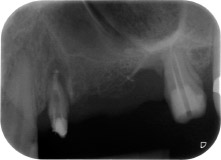

Fig. 1 : Patiente de 58 ans. Radio pré-opératoire montrant une lésion du parodonte apical à la dent 24 et une perte horizontale d'os alvéolaire dans le deuxième quadrant.

Une patiente de 58 ans se plaignait de douleurs et d'une mobilité accrue de la dent pilier 24 de son bridge. Présence d'une inflammation parodontale avec formation de poches de 7 mm de profondeur dans le sens mésiobuccal et de plus de 12 mm dans le sens distal, ainsi que d'une atteinte de la furcation au troisième degré. La radiographie a par ailleurs révélé une lésion parodontale étendue autour de la région apicale de la dent 24 ayant préalablement reçu un traitement endodontique (alio loco) (Fig. 1).

Un an plus tôt, les dents 25 et 26 avaient été extraites à la suite d'un traumatisme et pour cause d'atteinte endo-parodontale, avant la pose du bridge. Une lésion endo-parodontale combinée a été diagnostiquée pour la dent 24, d'étiologie incertaine. La patiente voulait conserver ses dents piliers 24 et 27 et refusait toute prothèse amovible à titre définitif, et même provisoire. Par conséquent, malgré un pronostic défavorable compte tenu des résultats des radios et des examens cliniques, il a été convenu de faire le maximum pour conserver les deux dents.